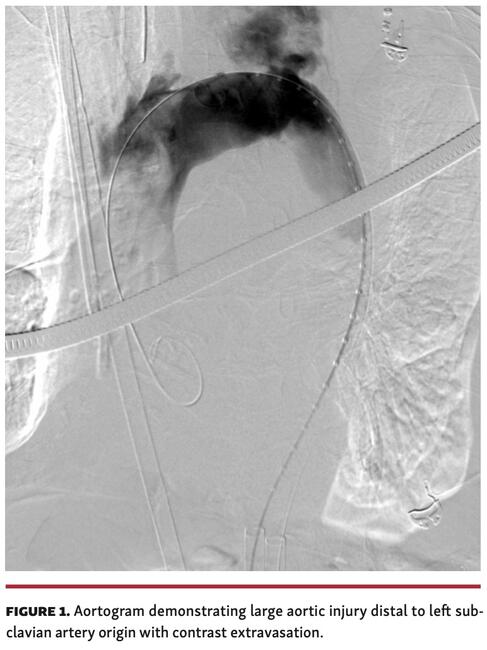

A 95-year-old man with severe symptomatic aortic stenosis was admitted for elective transcatheter aortic valve replacement (TAVR). He had balloon aortic valvuloplasty 1 year prior with aortic valve restenosis resulting in dyspnea on minimal exertion. The patient pursued TAVR for improvement in quality of life. His preprocedure computed tomography (CT) scan demonstrated moderate aortic and iliofemoral atherosclerosis. TAVR was performed in a hybrid theater with bilateral femoral arterial access. After crossing the aortic valve and recording peak-to-peak aortic valve gradient of 48 mm Hg, a stiff wire was placed in the left ventricle. The valve delivery system was passed over this, but would not easily cross the aortic arch. The patient became distressed and hypotensive. The aortogram demonstrated large aortic injury distal to the left subclavian artery origin with significant extravasation (Figure 1 and Video 1). The patient had pulseless electrical activity. Despite cardiopulmonary resuscitation, rapid blood transfusion, and covered stenting of aortic injury, the patient did not survive.